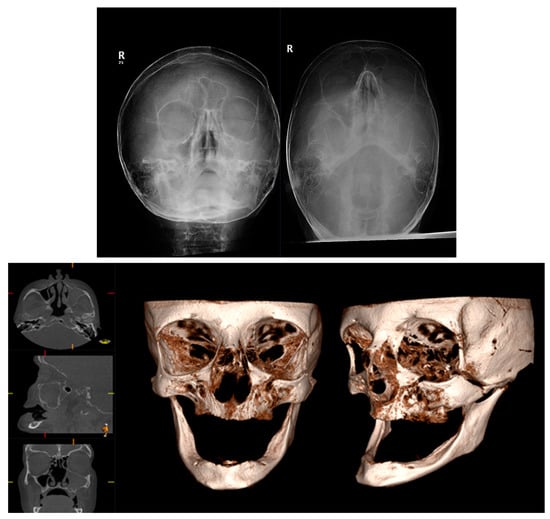

3.3. Cone Beam CT for Assessment of Frontal Sinus Fractures

3.4. Cone Beam CT for Assessment of Orbital Fractures